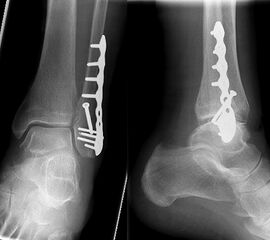

Die Versorgung von AO 44-B Frakturen erfolgt über einen längsverlaufenden lateralen Zugang. In der Regel gelingt eine suffiziente Stabilisierung mittels interfragmentärer Zugschraube (bei langem Frakturverlauf ggf. 2 Zugschrauben) und einer zusätzlichen Neutralisationsplatte (Abbildung 9 & 10).

Bei multifragmentären Frakturen (AO 44-B2.3) oder bei schlechter Knochenqualität sollte die Versorgung mittels winkelstabiler Plattenosteosynthese erwogen werden (Abbildung 11 & 12).